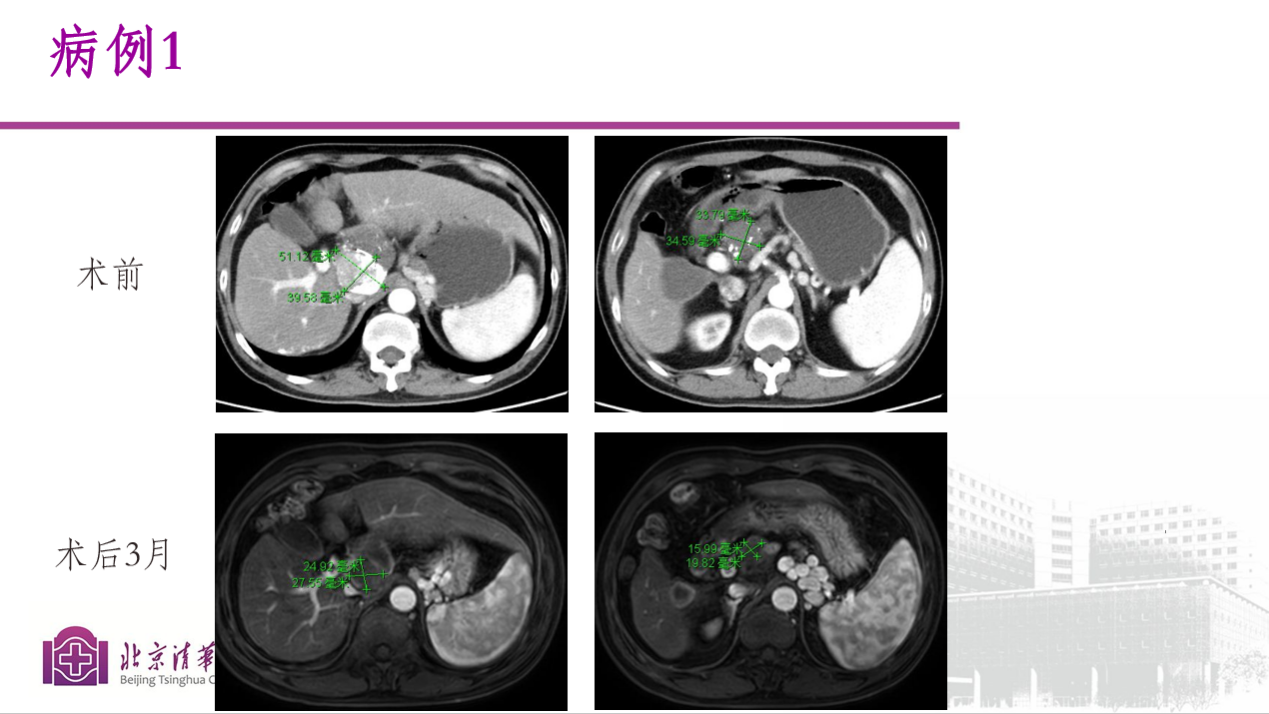

病例一:

53岁男性患者,肝尾状叶肝癌破裂TACE术后残留。经综合评估后,行钇90树脂微球治疗,,术中对肿瘤血管进行了优化处理策略,术后钇90微球分布良好,3个月肿瘤体积缩小接近70%